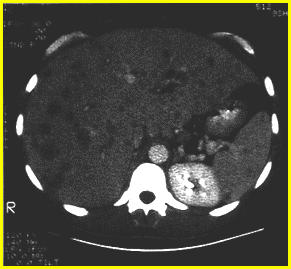

What sequelae of Cat Scratch disease (B. henselae) is characterized by the presence cystic, blood filled lesions in the liver and spleen parenchyma of immunocompromised patients? What are some other symptoms of this sequelae?

Hepatic or Splenic Peliosis

Other sx: Target organ enlargement, weight loss, nausea, fever, and elevated liver enzymes and alkaline phosphate.